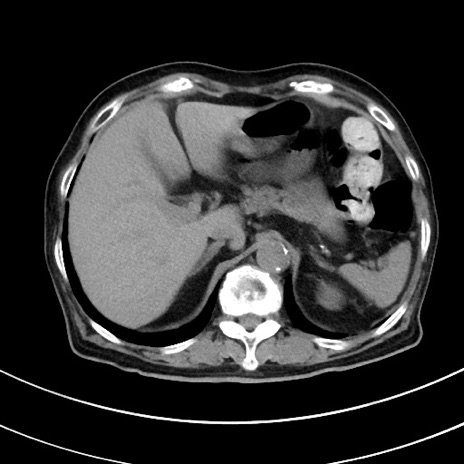

症例33(横断像)

【症例】70歳代 女性

【主訴】心窩部痛

【現病歴】延髄病変の精査・加療にて神経内科入院中。本日より心窩部痛あり。

【既往歴】虫垂炎

【身体所見】右下腹部を中心に圧痛と反跳痛あり。

【データ】WBC 10900、CRP 0.02